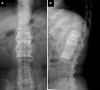

The concept of synovitis, acne, pustulosis, hyperostosis, osteitis (SAPHO) syndrome has been well clarified, after Chamot et al. suggested this peculiar disorder in 1987. The most commonly affected site in SAPHO syndrome is the anterior chest, followed by the spine. However, the clinical course and taxonomic concept of SAPHO spinal lesions are poorly understood. This study was performed to analyze: (1) the detailed clinical course of spinal lesions in SAPHO syndrome, and (2) the relationship between SAPHO syndrome with spinal lesions and seronegative spondyloarthropathy. Thirteen patients with spondylitis in SAPHO syndrome were analyzed. The features of spinal lesions were a chronic onset with a slight inflammatory reaction, and slowly progressing non-marginal syndesmophytes at multi spinal levels, besides the coexistence of specific skin lesions. SAPHO syndrome, especially spinal lesions related to palmoplantar pustulosis, can be recognized as a subtype of seronegative spondyloarthropathy.